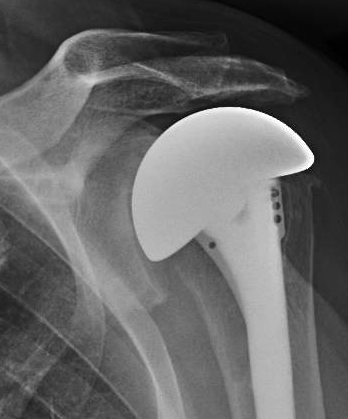

At four years after surgery, he could perform 8 of the 12 SST functions and had the radiographs shown below. Note the impaction grafted humeral stem and the articulation of the prosthesis with the undersurface of the coracoacromial arch.